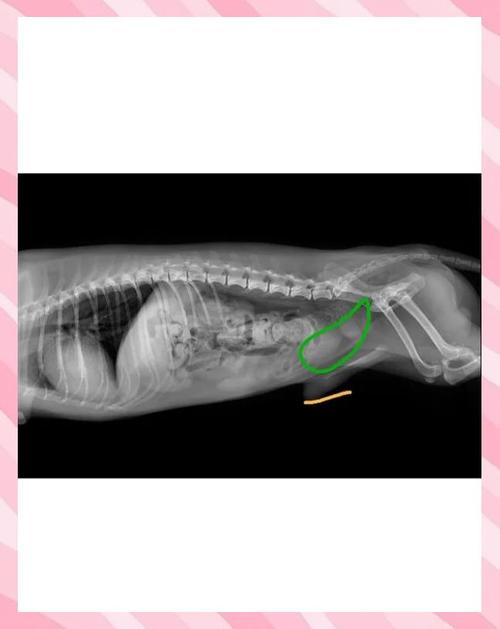

犬前列腺肥大临床症状 前列腺肥大是老龄公犬前列腺功能障碍的常见病。6岁以上的公犬有60%都有不同程度的前列腺肥大。临床特征为排便困难。主要症状是里急后重、排便困难或便秘,患犬频频努责,仅排出少量黏液。偶有少尿、血尿和膀胱膨满现象。

〖Two〗、前列腺肥大是老龄公犬前列腺功能障碍的常见病。6岁以上的公犬有60%都有不同程度的前列腺肥大。临床特征为排便困难。主要症状是里急后重、排便困难或便秘,患犬频频努责,仅排出少量黏液。偶有少尿、血尿和膀胱膨满现象。有的病例由于过度努责,腹压加大,致使肥大的前列腺进入骨盆腔而形成会阴疝。